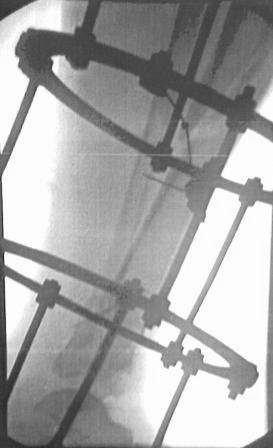

Больной 41г переведен из ЦРБ, травма в результате ДТП- 5 дней назад, произведена ПХО раны, наложена гипсовая повязка.

Об-но; начиная с с/з голени продольно - почти циркулярная рана, с признаками инфицирования - покраснение, отечность, усиление боли, местная т-ра и мутные кровянистые выделения из раны, и выраженная деформация голени. В отд нашей коллегой в экстренном порядке в задней поверхности голени щвы распушены, выпушено около 50мл мутной гематомы, АВФ, умеренная дистракция, антибиотики, и т.д.

Наш план; после устранения воспалительных процессов, перемонтаж аппарата, репозиция оставшихся смещений спицами с упорной плошадкой и стабилизация аппарата, дальше по обстановке.

План довольно оптимистичный. Если инфекция легко купируется, то действительно стабилизировать спицами дистальный отломок большеберцовой кости, освободить стопу.

2.Не могу, потому что аппарат Илизарова наложен нашей молодой коллегой в экстренном порядке, и несовсем удачно и с ошибками, но главную функцию для данного случая -дистракцию выполняет,( поэтому я писал, что будем делать перемонтаж.)